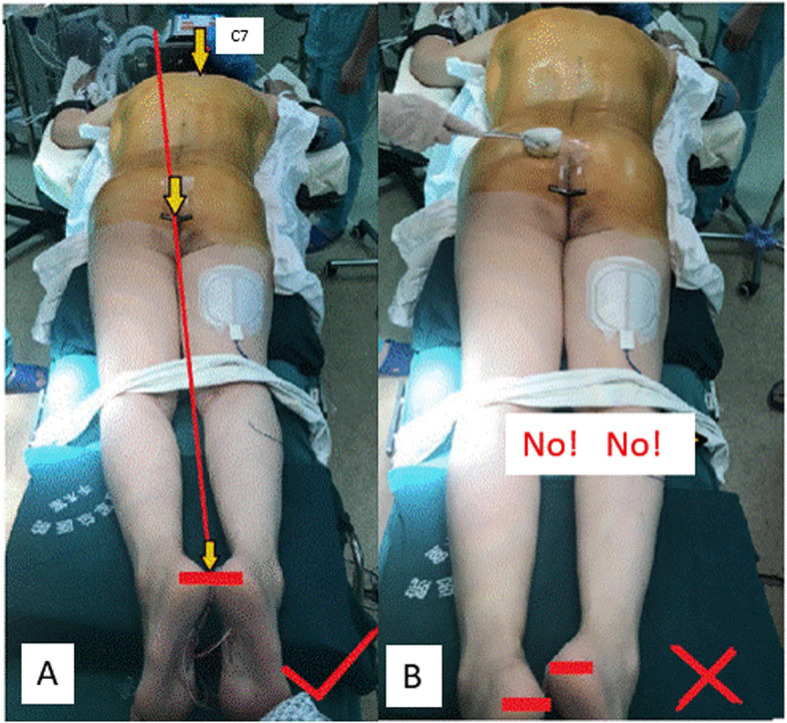

Anesthesia, positioning and establishing lower body part aligner

After general endotracheal anesthesia performed, the patient was placed in a prone position. First, the heel bottoms were adjusted to be flush with each other, then bilateral ankles and knees were made symmetrical and at the same level, respectively. Thus, the midpoints between two heels/two ankles/two knees, and gluteal cleft were made on the same line, which is the lower body part aligner (Fig. 1a). To establish this lower body part aligner, upper body part (body trunk) of severe spinal deformity patients was usually placed partially off the operation table and supported by an added frame. In contrast to priority of upper body part positioning in common spinal surgeries, positioning of lower body part was prioritized in this technique of ours, which set a basis for spinal deformity to be corrected. The common mistake is to only focus on positioning of the upper body part and ignore the presence of iatrogenic discrepancy of leg length (Fig. 1b), which might lead to postoperative coronal imbalance in standing position.